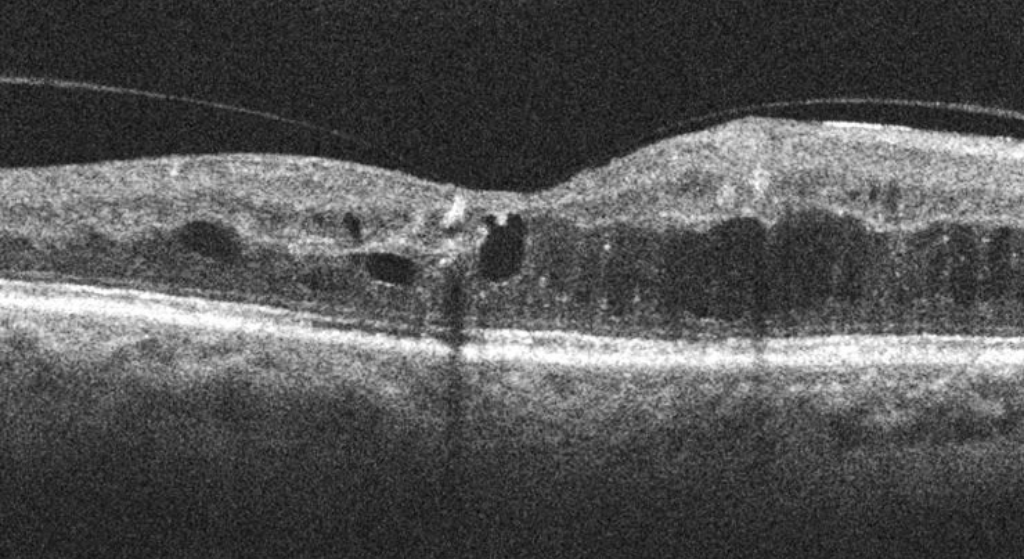

Existen diferentes opciones para tratar el edema macular, el tratamiento a aplicar es determinado en función del paciente, las causas, y el tipo y grado de severidad de la patología; en los casos más leves, puede ser suficiente la prescripción de colirios, en otros casos pueden aplicarse inyecciones intravítreas de fármacos ya sea antiangiogénicos o corticoide, y en otros puede ser necesaria la aplicación de láser (fotocoagulación) para “sellar” los puntos. finalmente, en aquellos casos de mayor gravedad, puede ser necesario recurrir a la cirugía y practicar una vitrectomía.